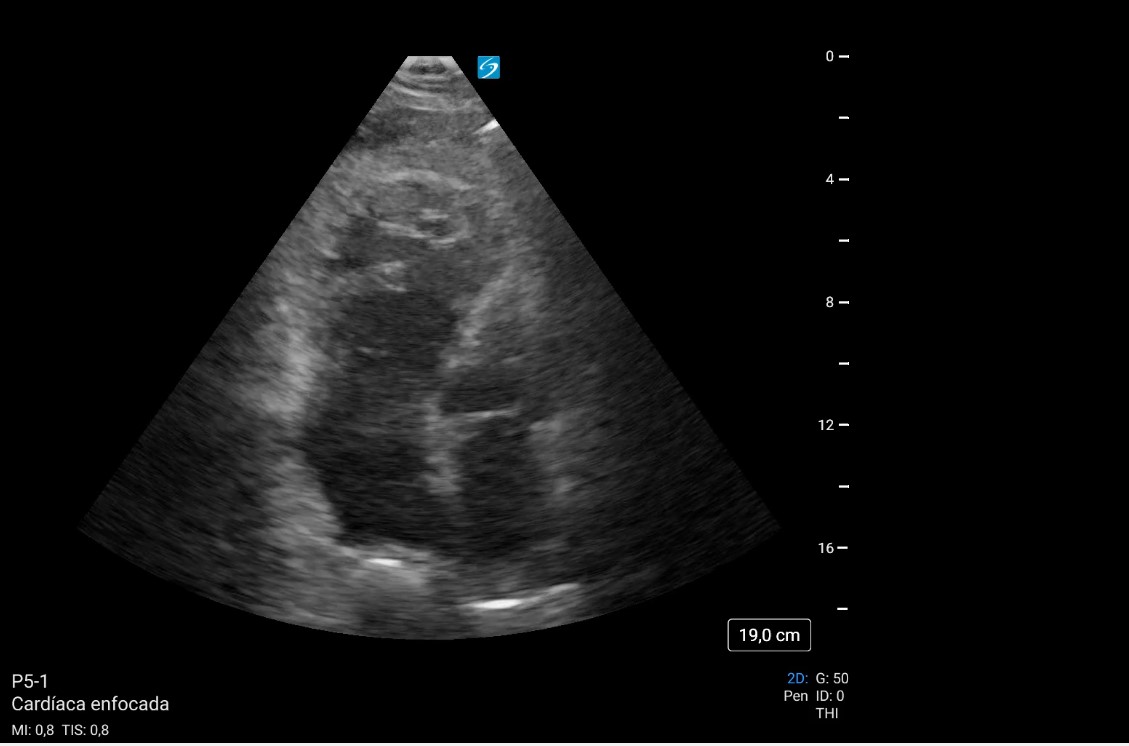

Se decide realizar ecocardiografía clínica para valorar las cavidades cardíacas, observando datos de sobrecarga derecha y una imagen compatible con trombo en ventrículo derecho: signos indirectos de TEP, confirmando alta sospecha, iniciando anticoagulación y solicitando angioTC directamente.

El angioTC pulmonar solicitado confirmó nuestra sospecha: TEP bilateral, proximal y distal, con signos de hipertensión pulmonar y sobrecarga cardíaca derecha. Posteriormente, ingresó en Medicina Intensiva, donde se confirmaron la presencia de trombo intraventricular de 7-8 cm y la TVP poplítea. Se continuó con anticoagulación y el paciente evolucionó favorablemente.